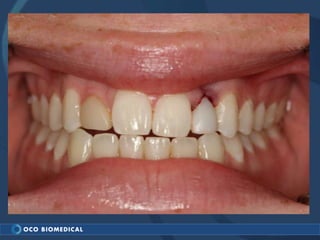

A 3.0mm dental implant was placed to replace congenitally missing maxillary lateral incisors. Dr. Tim Kosinski used a 1.8mm pilot bur and tissue punch to prepare the osteotomy site, then placed the implant by hand and seated it with a torque wrench. After ensuring the implant trajectory was within the restorative envelope, an acrylic coping was placed for temporary fabrication. At the 1 week post-op appointment, excellent soft tissue response and papilla formation were observed, and a final impression was taken to send to the lab for crown fabrication.